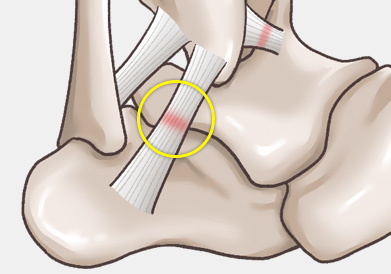

발목 인대는 발목 관절의 안정성을 유지하고, 발의 과도한 움직임을

제한하여 발목 관절을 보호하는 역할을 합니다.

주로 다음 그림처럼 내반(inversion)에 의해 바깥쪽 인대가 파열되는 경우가 흔하며, 그 중에서도 전거비인대 및 종비인대의 손상 여부가 수술을 결정하는 데 가장 중요합니다.